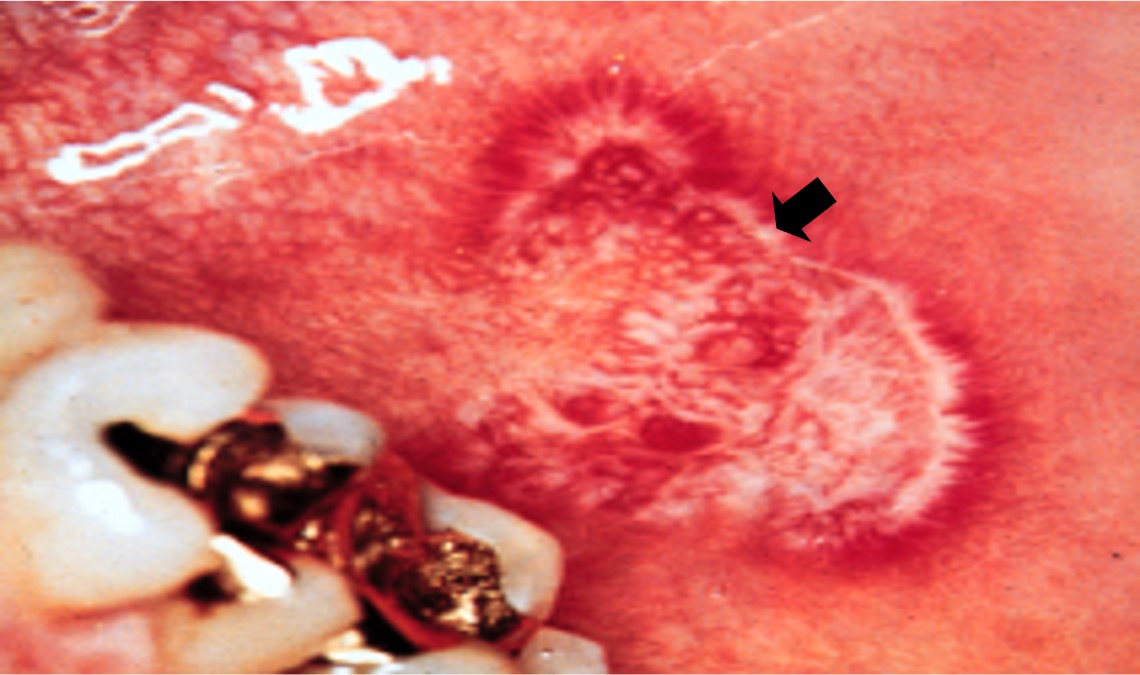

特征性表现:红色病变呈萎缩或浅表糜烂的不规则红斑,其边缘可见放射状排列的白色纤细条纹(图11.2-13)。

图11.2-13 慢性盘状红斑狼疮